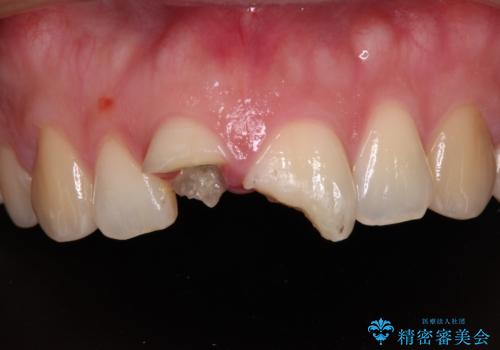

- 転倒により前歯を折ってしまったとのことで来院された患者様です。

右側の前歯は歯茎の中にまで及ぶ深い破折線があり、神経組織は既に失活していました。

左側の前歯は大きく歯冠が欠けてはいましたが、神経の生活反応が認められました。